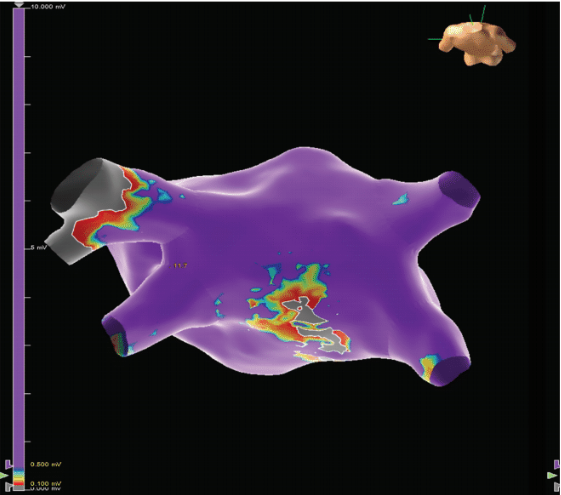

the LA, LA thrombus, and success of the LAA closure. The patient presented in AF. The patient was placed under general anesthesia and successfully cardioverted to sinus rhythm. Radiofrequency (RF) ablation of the CTI with the TactiCath Contact Force Ablation Catheter, Sensor Enabled (Abbott) was performed, which demonstrated medial to lateral block of about 151 ms. Block across the linear ablation line was confirmed with the EnSite X System (Abbott). We then proceeded to the LA via transseptal puncture with the VersaCross Transseptal Platform (Baylis Medical). Mapping of the LA was performed utilizing the Advisor HD Grid Mapping Catheter, Sensor Enabled (Abbott). The pre-LA endocardial ablation map (Figure 2) showed areas of scar creation near the middle of the posterior wall but healthier tissue near the veins, as well as areas of the epicardial region where there was some difficulty. The Advisor HD Grid catheter was then exchanged for the Arctic Front cryoballoon catheter (Medtronic) to allow for single-shot ablation of the PVs. After PVI, the system was exchanged for the Advisor HD Grid catheter and mapping was again performed in the LA. The additional lesion sets from PVI were displayed on the map and the Advisor HD Grid catheter was exchanged for the TactiCath catheter. Linear RF lesions were then made across the roof connecting the left and right superior PVs as well as the floor of the LA connecting the left and right inferior PVs. There were a few areas of presumed epicardial breakthrough points on the posterior wall, and further RF applications in those areas resulted in complete posterior wall isolation (Figure 3). Once complete, another EP study was performed with isoproterenol infusion and no additional arrhythmias were inducible. All catheters and sheaths were removed, and hemostasis was achieved with a figure-of-8 suture. There were no complications from the endocardial portion of the procedure. The patient was ambulatory within 2 hours and discharged home the day of the procedure.